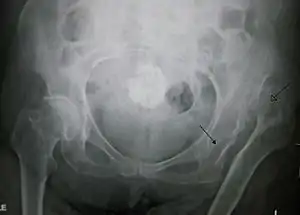

| X-ray showing a joint dislocation of the left hip. | |

Typically, people with hip dislocations present with severe pain and an inability to move the affected leg.[1][4] Diagnosis is made by physical exam and plain X-rays of the hips. A CT scan is recommended following reduction to rule out complications. Complications include osteonecrosis, femoral head fractures, and posttraumatic osteoarthritis.[12][13]

An anterior-posterior (AP) X-ray of the pelvis and a cross-table lateral X-ray[24] of the effected hip are ordered for diagnosis.[4][5][16] The size of the head of the femur is then compared across both sides of the pelvis. The affected femoral head will appear larger if the dislocation is anterior, and smaller if posterior.[7] A CT scan may also be ordered to clarify the fracture pattern.[20]